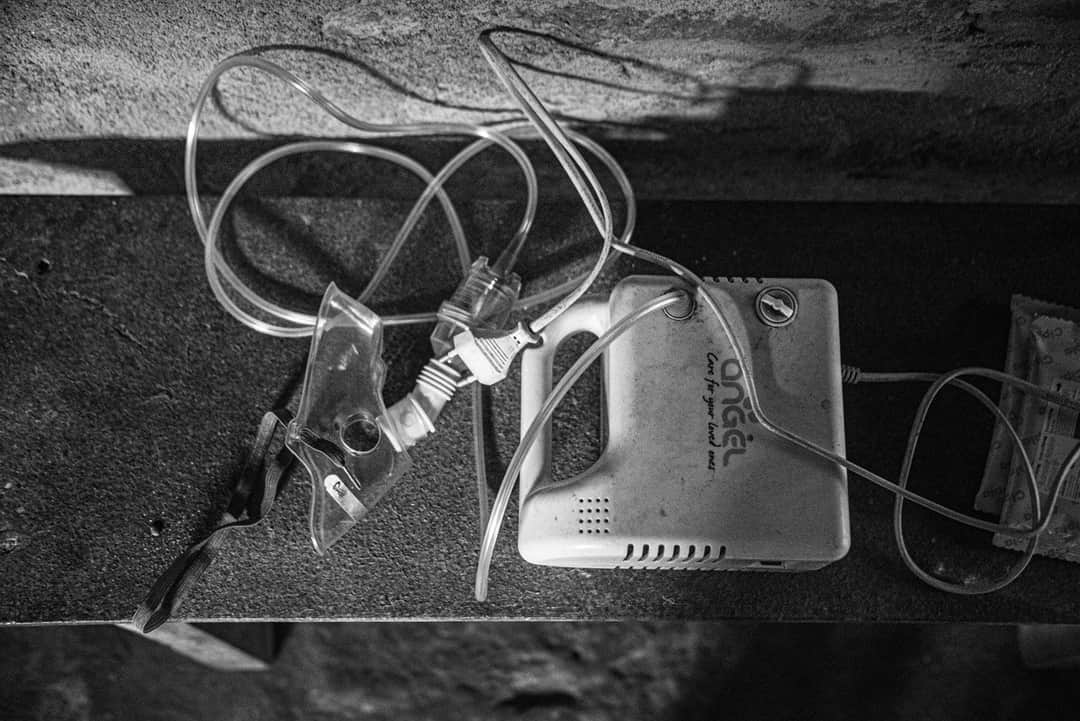

55 ਸਾਲਾ ਇਸ ਵਿਅਕਤੀ ਨੂੰ ਨਵੰਬਰ 2022 ਵਿੱਚ ਇੱਕ ਜਾਂਚ ਦੌਰਾਨ ਸਿਲੀਕੋਸਿਸ ਰੋਗ ਹੋਣ ਦਾ ਪਤਾ ਲੱਗਾ ਸੀ ਜੋ ਫੇਫੜਿਆਂ ਦੀ ਲਾਇਲਾਜ ਬਿਮਾਰੀ ਹੈ। ''ਮੈਂ ਆਉਣ ਵਾਲ਼ੀਆਂ ਚੋਣਾਂ ਬਾਰੇ ਸੋਚਣ ਦੀ ਹਾਲਤ 'ਚ ਨਹੀਂ ਹਾਂ। ਮੈਨੂੰ ਆਪਣੇ ਪਰਿਵਾਰ ਦੀ ਹਾਲਤ ਬਾਰੇ ਚਿੰਤਾ ਏ," ਉਹ ਕਹਿੰਦੇ ਹਨ।

ਦੋਵਾਂ ਨੇ ਇੱਕ-ਡੇਢ ਸਾਲ ਲਗਾਤਾਰ ਉਨ੍ਹਾਂ ਫ਼ੈਕਟਰੀਆਂ ਵਿੱਚ ਕੰਮ ਕੀਤਾ ਜਿੱਥੇ ਉਹ ਸਿਲਿਕਾ ਧੂੜ ਦੇ ਸਿੱਧਿਆਂ ਸੰਪਰਕ ਵਿੱਚ ਆਉਂਦੇ ਰਹੇ ਤੇ ਜਿੱਥੇ ਉਨ੍ਹਾਂ ਦੀ ਸਿਹਤ ਦਾ ਨੁਕਸਾਨ ਹੋਣ ਦੇ ਨਾਲ਼-ਨਾਲ਼ ਉਨ੍ਹਾਂ ਨੂੰ ਪੈਸਿਆਂ ਦਾ ਨੁਕਸਾਨ ਵੀ ਝੱਲਣਾ ਪਿਆ। ਉਨ੍ਹਾਂ ਨੂੰ ਮੁਆਵਜ਼ਾ ਨਹੀਂ ਮਿਲ਼ਦਾ ਕਿਉਂਕਿ ਰੈਮਿੰਗ ਮਾਸ ਦੀਆਂ ਬਹੁਤੇਰੀਆਂ ਫ਼ੈਕਟਰੀਆਂ ਡਾਇਰੈਕਟੋਰੇਟ ਆਫ਼ ਫ਼ੈਕਟਰੀਜ਼ ਕੋਲ਼ ਰਜਿਸਟਰਡ ਨਹੀਂ ਹਨ ਤੇ ਜੋ ਹਨ ਵੀ ਉਹ ਵੀ ਨਾ ਤਾਂ ਨਿਯੁਕਤੀ ਪੱਤਰ ਜਾਰੀ ਕਰਦੀਆਂ ਹਨ ਤੇ ਨਾ ਹੀ ਪਛਾਣ ਪੱਤਰ। ਅਜਿਹੀਆਂ ਬਹੁਤ ਸਾਰੀਆਂ ਫ਼ੈਕਟਰੀਆਂ ਅਸਲ ਵਿੱਚ ਗੈਰ-ਕਾਨੂੰਨੀ ਜਾਂ ਅੱਧ-ਪਚੱਧੇ ਕਾਨੂੰਨੀ ਦਾਇਰੇ ਹੇਠ ਹਨ। ਇਨ੍ਹਾਂ ਖੇਤਰਾਂ ਵਿੱਚ ਕੰਮ ਕਰਨ ਵਾਲ਼ੇ ਕਾਮੇ ਵੀ ਰਜਿਸਟਰਡ ਨਹੀਂ ਹਨ।